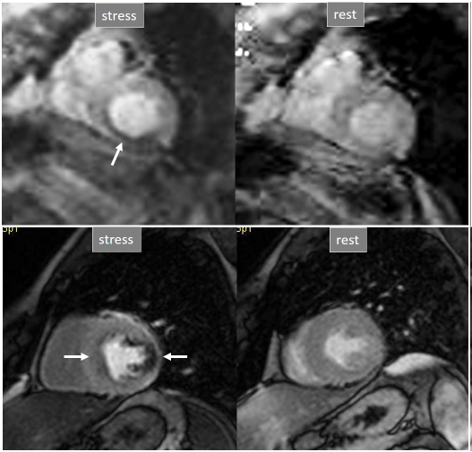

Perfusion defects in different territories can be detected in case of multivessel disease (Fig. 7) and, in patients with severe 3-vessel CAD, the perfusion study may show a global, intense, persistent defect which is readily recognizable (Fig. 8).

Fig. 7.Two-vessel perfusion defect. Stress perfusion defects at the anterior (white arrows) and inferior (black arrows) walls, not present at rest. Angiography (right panels) shows significant stenoses (white arrows) of the LAD (upper panel) and the right coronary artery (RCA) (lower panel).

Fig. 8.Three-vessel perfusion defect. Stress and rest studies in a patient with severe left main and 3-vessel CAD (arrows, on the right panels) showing an inducible perfusion defect in most, if not all, of the myocardial segments during vasodilatory stress.